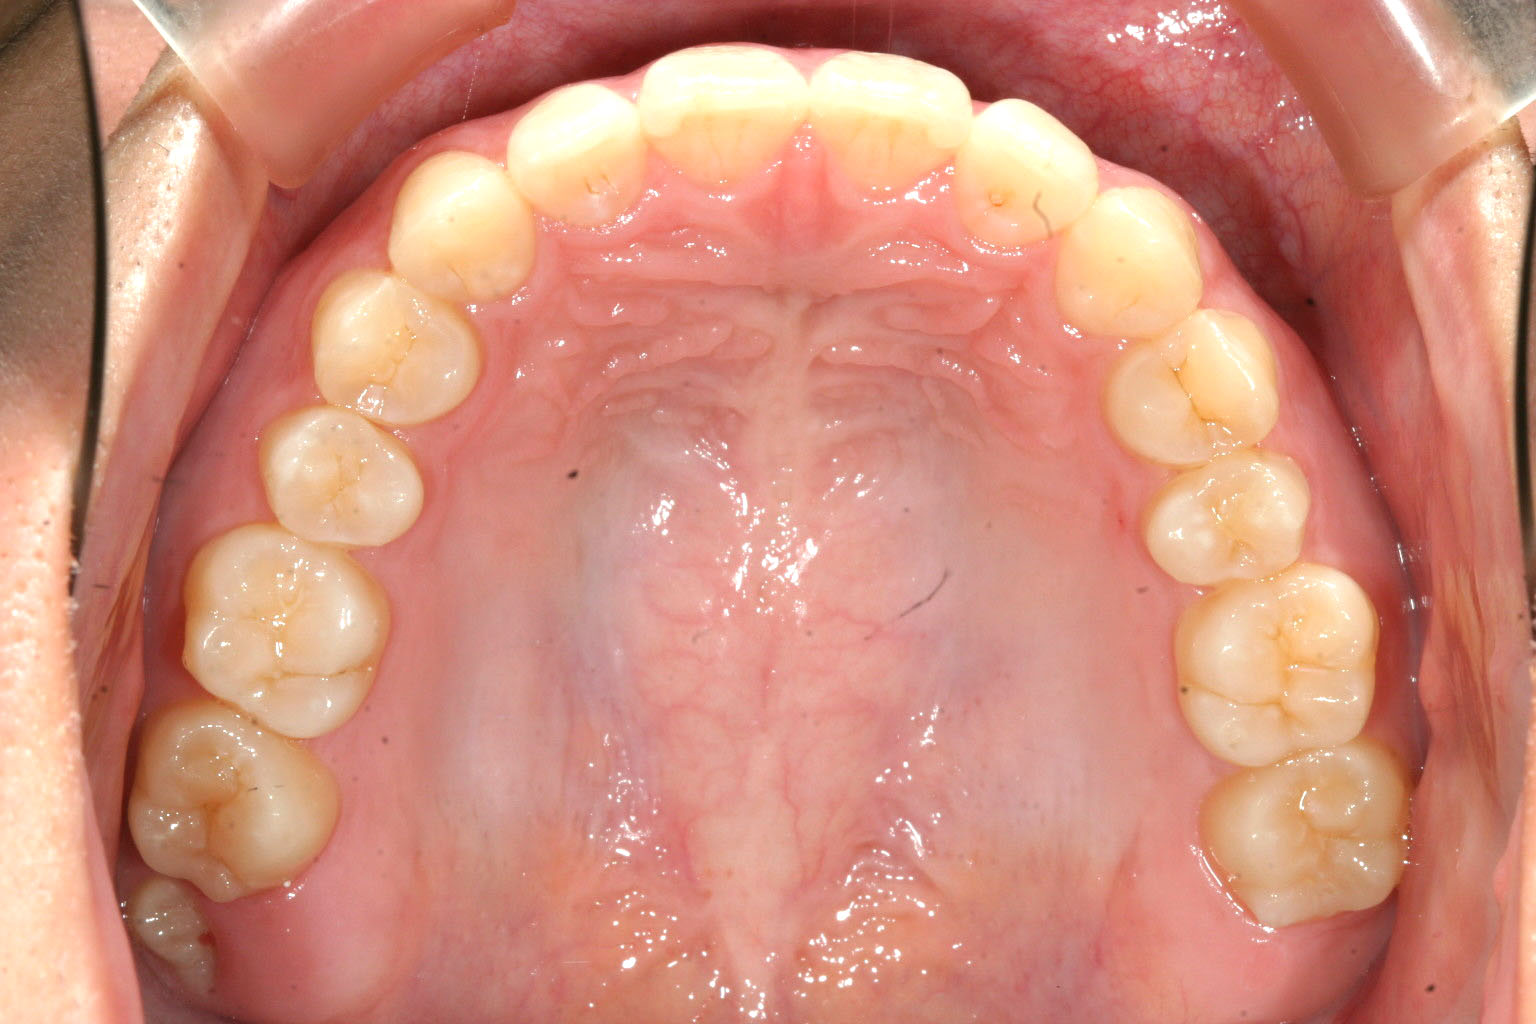

上顎が綺麗に並びました。

出っ歯観も無くなり綺麗に並びました。